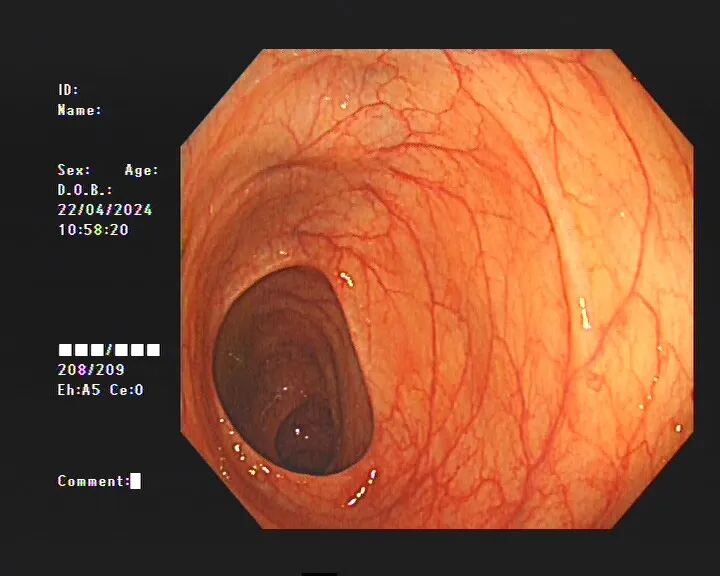

據(jù)醫(yī)生介紹,臨床上許多患者自行口服藥物后篩查腸鏡均有不同程度的結(jié)腸黑變病。正常的結(jié)腸黏膜就像我們的口腔黏膜一樣,是淡紅色的,看起來光滑平坦,黏膜表面的小血管紋理清晰可見。而結(jié)腸黑變病的腸黏膜色澤呈現(xiàn)棕色、褐色,有豹紋或者蛇皮一樣的條狀紋,嚴(yán)重的甚至?xí)兂珊谏?/span>

正常的腸道